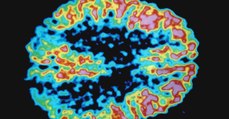

Maladie d’Alzheimer : une nouvelle piste prometteuse pour mieux comprendre son développement

Maladie d'Alzheimer : Le sommeil profond jouerait un rôle dans le développement de la maladie